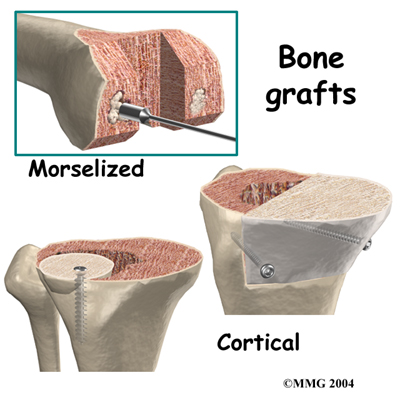

Revision joint replacements are much different from primary joint replacements. One reason that revision procedures are not routine is that there is almost always bone loss around the primary prosthesis. The surgeon deals with this problem by placing a or some other material around the artificial joint to reinforce the bone. This bone graft may come from your own body, such as bone taken from the pelvis during the same operation. This type of graft is called an autograft.

Revision joint replacements are much different from primary joint replacements. One reason that revision procedures are not routine is that there is almost always bone loss around the primary prosthesis. The surgeon deals with this problem by placing a or some other material around the artificial joint to reinforce the bone. This bone graft may come from your own body, such as bone taken from the pelvis during the same operation. This type of graft is called an autograft.

If the amount of bone needed is too large to take from your body, your surgeon may choose to use bone graft from the bone bank. This type of bone graft has been taken from someone else and placed in the bone bank. This type of transplant is called an allograft.

After application of bone and other materials to rebuild the tibia and/or femur, a new prosthesis is implanted. It is challenging to imitate the natural shape of the bones after rebuilding the bone, so a specially designed prosthesis is usually needed. All of this is carefully planned by the surgeon before the operation.